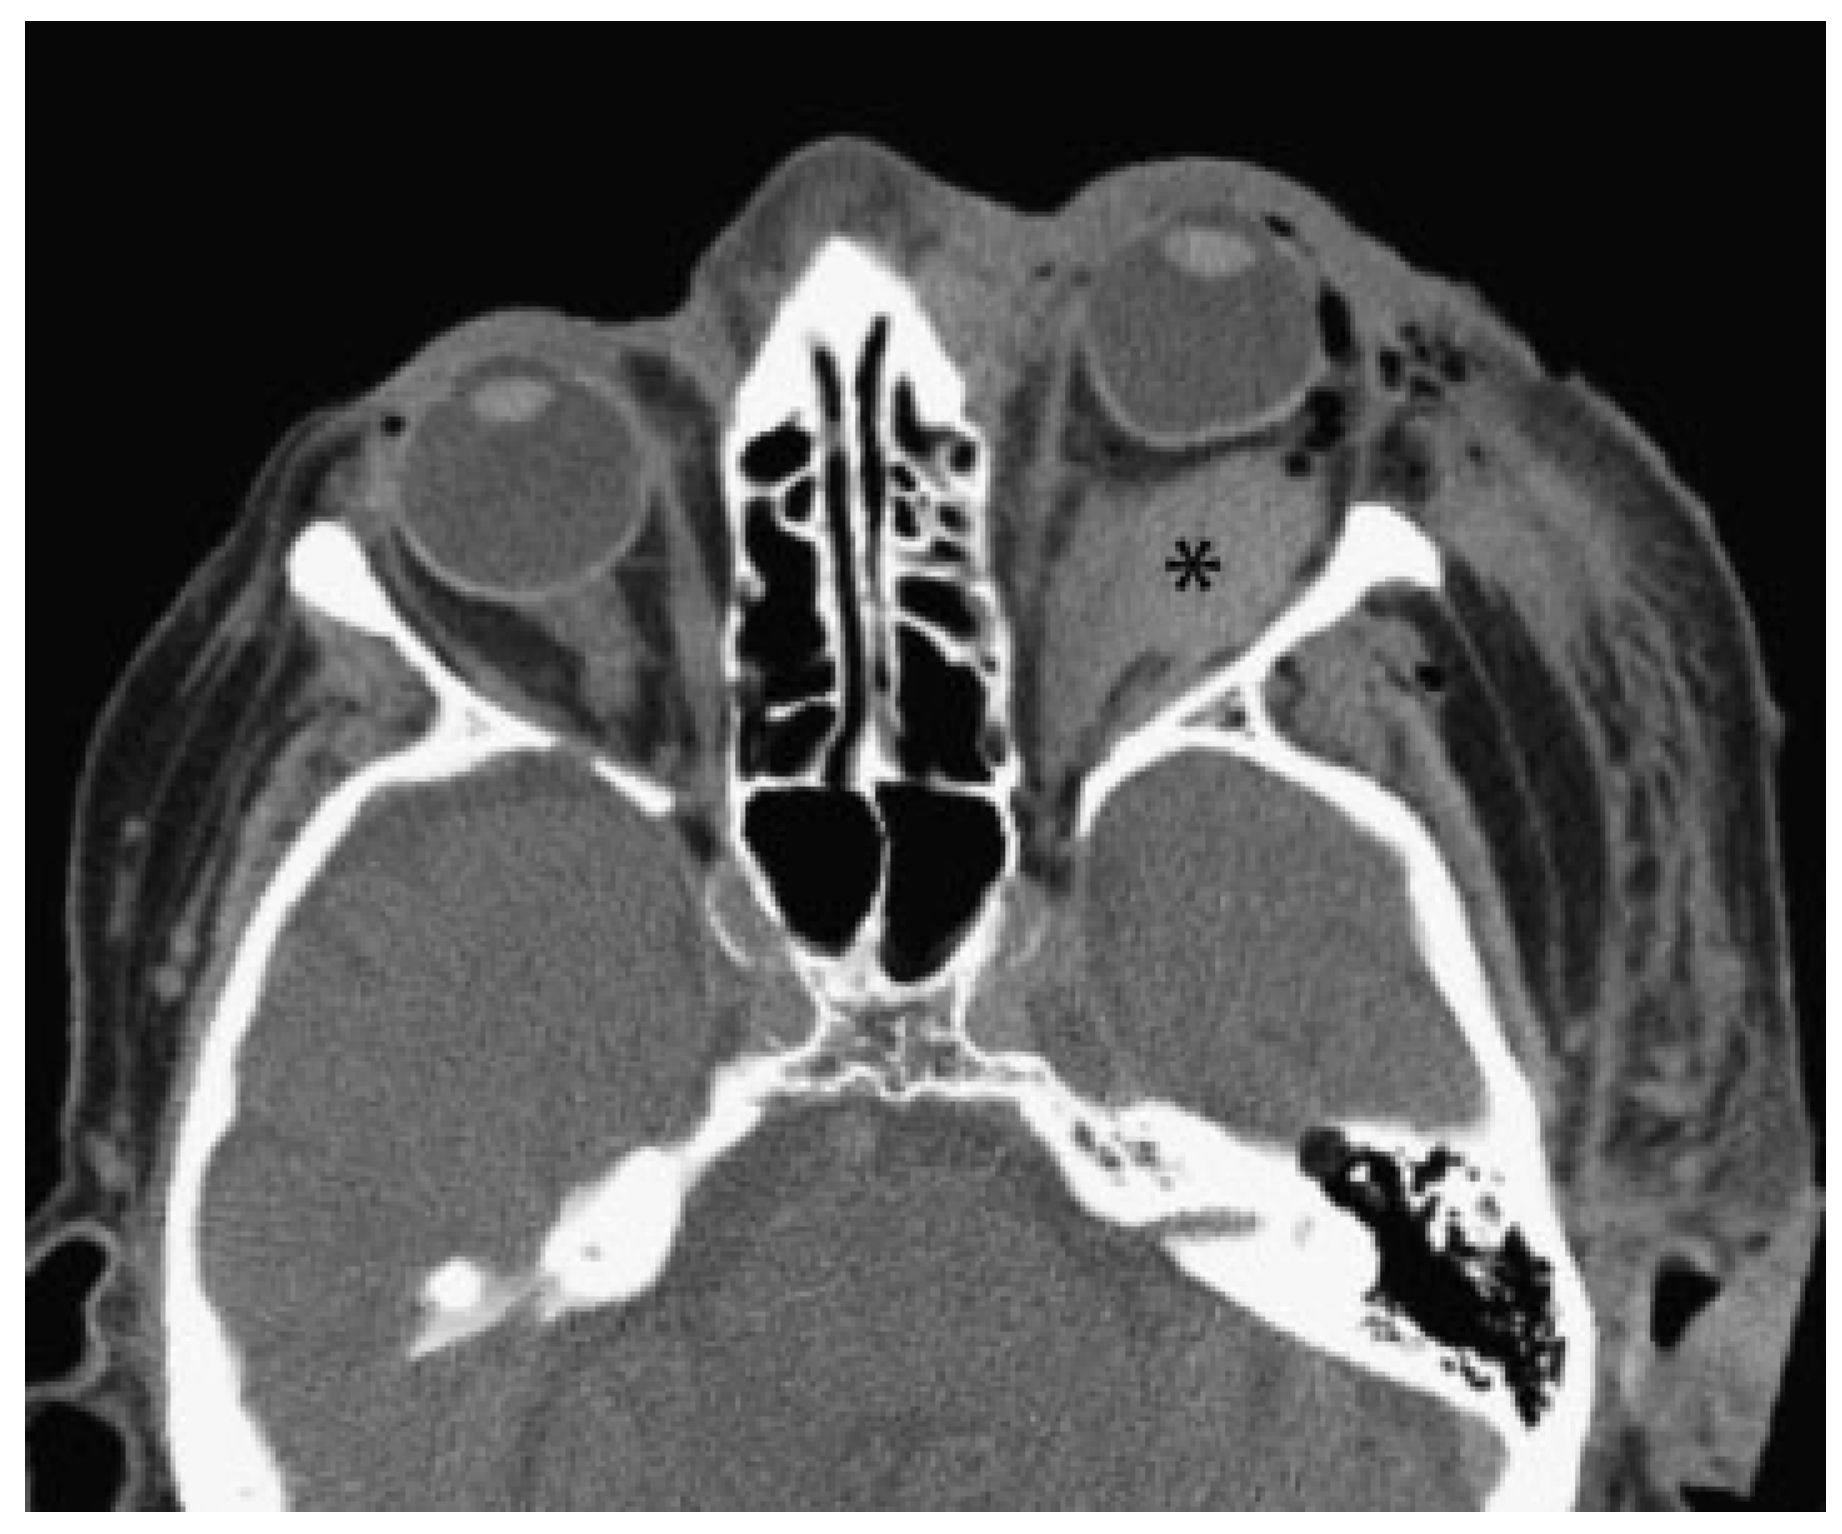

- Primary signs: fracture of the optic nerve canal; fracture in the retrobulbar region; hematoma, swelling, or disconti- nuity of the optic nerve; hematoma in the posterior third of the orbit.

- Secondary signs: shading of the sphenoidal sinus or of the posterior ethmoidal cells; air–fluid level in the maxillary sinus; epidural hematoma of the temporobasal region.

- Concomitant injuries: lamina papyracea; frontal sinus; zygomatic bone; orbital floor; orbital roof; air collection below the frontonasal region, optic chiasm, cavernous sinus, or posterior of the big wing of the sphenoid bone; contusions; subarachnoid or subdural hemorrhage.